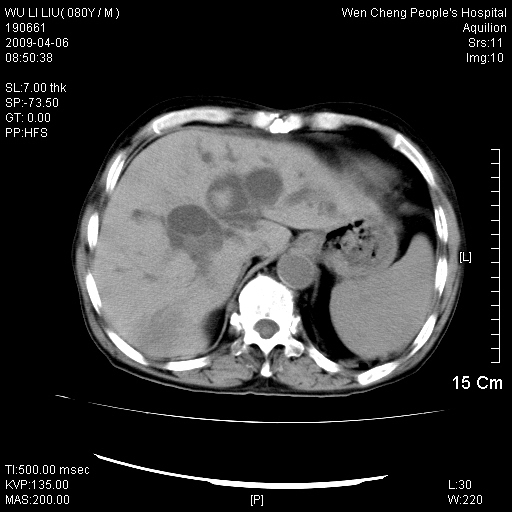

以下是引用zjzjr在2009-4-7 12:13:00的发言:[br]支持多发性转移瘤,右股骨颈骨折,腰椎亦有压缩性骨折.肝内胆管结石伴胆内外胆管扩张,左肾结石.

以下是引用liaoqiang在2009-4-7 8:44:00的发言:[br]考虑多发性骨髓瘤伴肝肺转移、肝内胆管结石、左肾结石、右股骨颈骨折。

以下是引用余辉在2009-4-7 8:52:00的发言:[br]椎骨及骨盆骨质疏松,骨破坏主要累及椎体,各骨破坏较广泛,各病灶边缘均较清晰锐利,血沉增快,白细胞增高.支持考虑多发骨髓瘤,建议查本尿周氏蛋白.[br]胆内胆管及左肾结石[br]右股骨颈骨折,考虑病理性